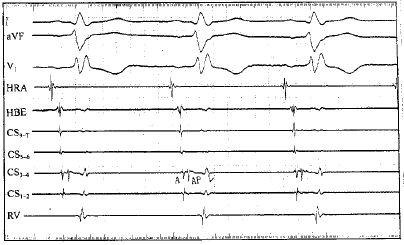

附图 冠状静脉窦电极记录的旁路电位。A:心房波 AP:旁路电位 V:心室波

患者女性,26岁。“频繁阵发性心动过速”史10年,体表心电图无预激表现。入院后检查无器质性心脏病。患者继往接收2次射频导管消融术,包括心室面标测和心房间隔穿刺心房面标测消融均失败。局部麻醉下行心内电生理检查,窦性心律时冠状静脉窦远端电极(CS1-2)记录到A波之后的旁路电位,旁路电位与V波之间有一段时间距离,V波无提前(附图),心房程序刺激A波之后的旁路电位持续存在,而V波无提前,体表心电图无预激表现。心室程序刺激旁路逆传时冠状静脉窦远端电极可以记录到V波和A波之间的旁路电位,无逆传时旁路电位消失。心动过速时同样可以记录到V、A波之间的旁路电位。先行经股动脉逆行法在心室面标测,多次放电消融未成功,改行经冠状静脉窦标测,在标测电极记录到A波之后的旁路电位时,以15 W消融1.5秒后旁路电位消失,2秒后心室起搏示室房分离,旁路阻断,心动过速不再诱发。

本例患者窦性心律时记录到A波之后的旁路电位说明旁路具有前传功能,而体表心电图无预激表现,心内局部电极V波也无提前,说明旁路室端存在单向阻滞,国内外尚未见报告,实属罕见。作者认为产生单向阻滞的原因可能是旁路靠近心外膜,该处组织传导功能较差,心室肌不能有效激动所致。本例患者记录的这种电生理现象即室端单向阻滞可能是产生隐匿性旁路的原因之一。